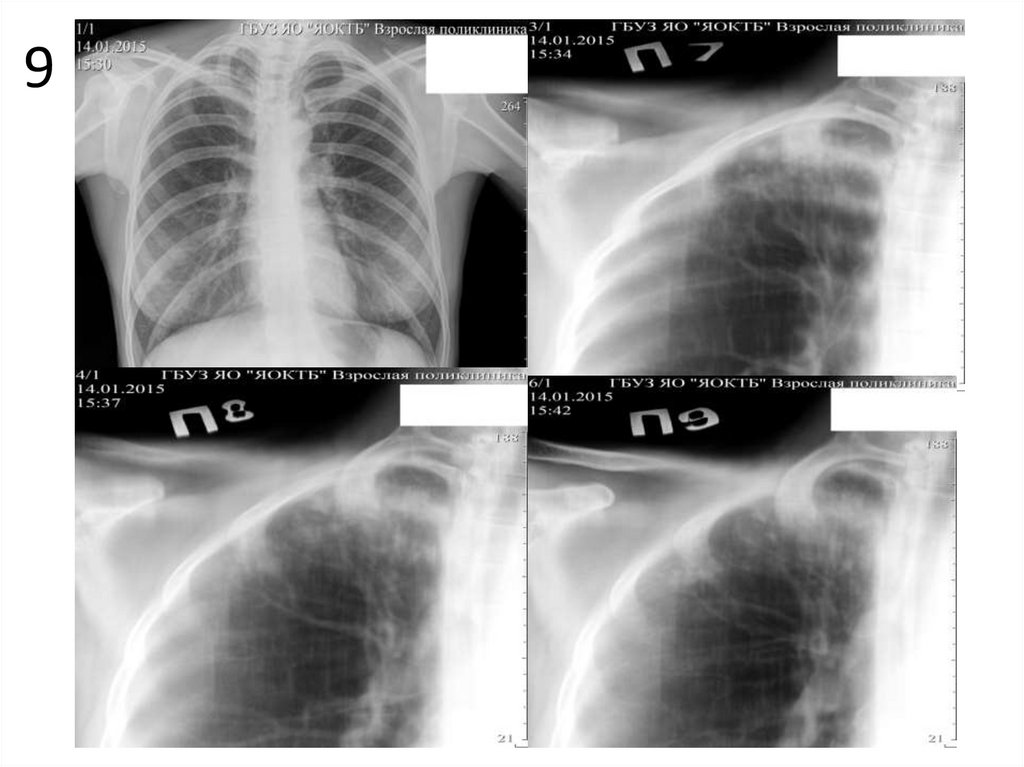

9

1. Опишите представленные снимки, выделите основной

рентгенологический синдром.

2. Имеются ли признаки туберкулеза на данных снимках?

Если да, перечислите их.

3. При наличии признаков туберкулеза определите форму,

фазу процесса, укажите возможные осложнения.